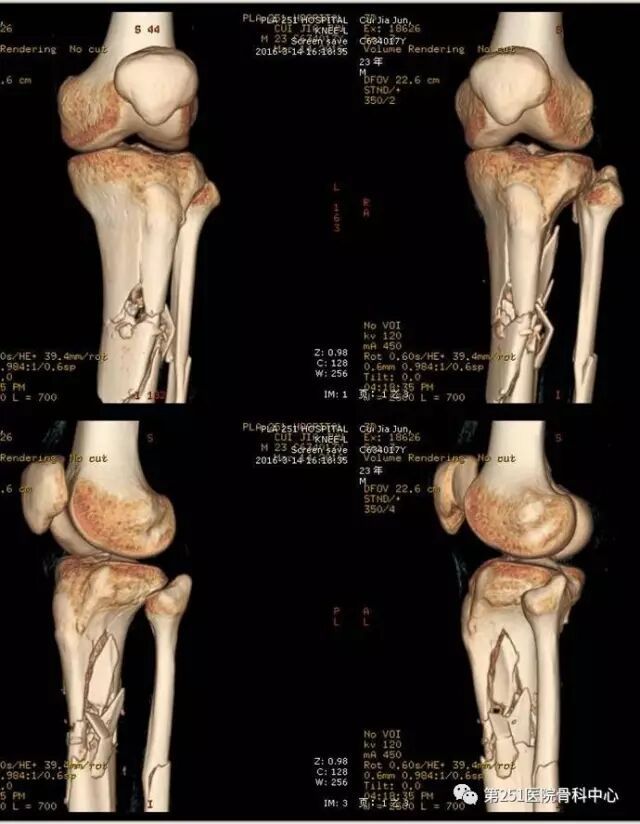

病例8:男性,24岁,车祸伤,胫腓骨近段粉碎性骨折。

![]()